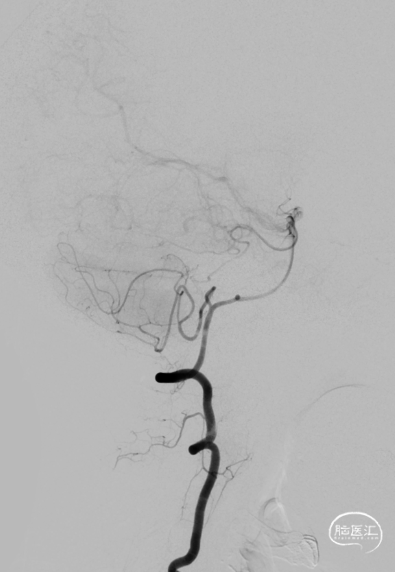

2024年4月1日 DSA

L ICA

L ICA

Pre-OP

Post-OP